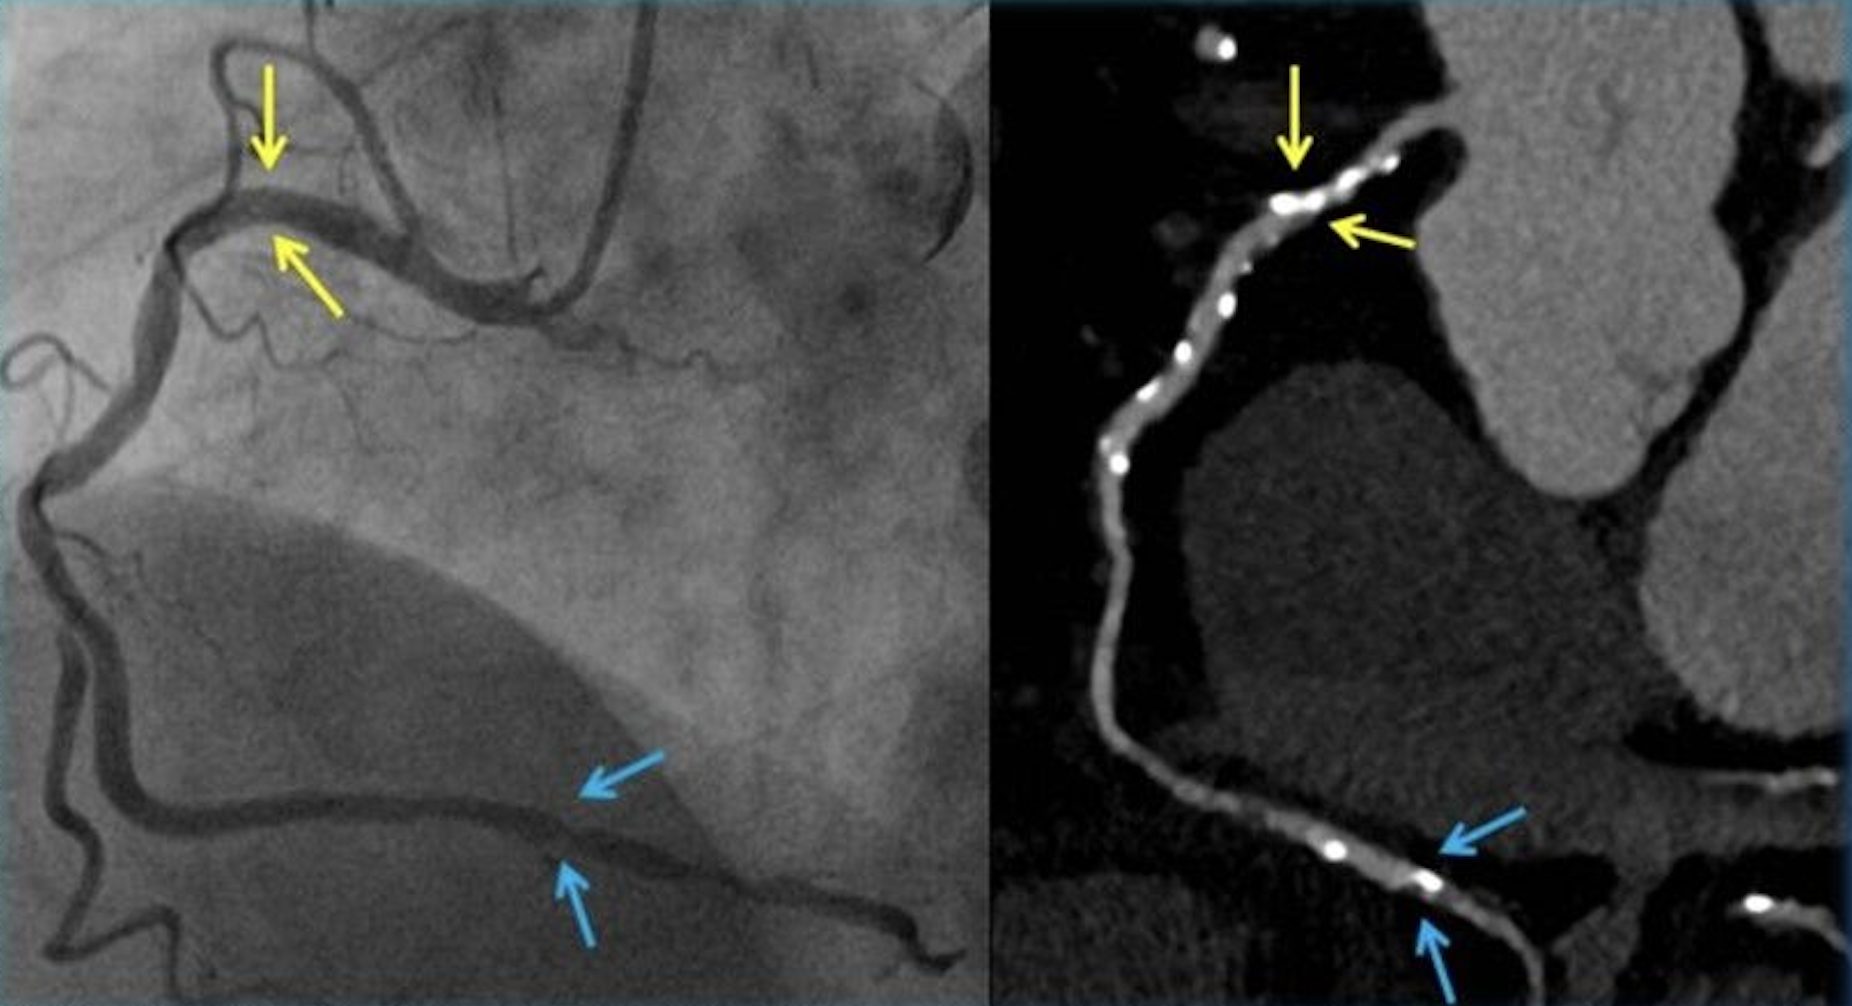

سی تی آنژیوگرافی قلب

آنژیوگرافی یا سی تی آنژیوگرافی! کدام بهتر است؟

آشنایی با شباهت ها و تفاوت های آنها